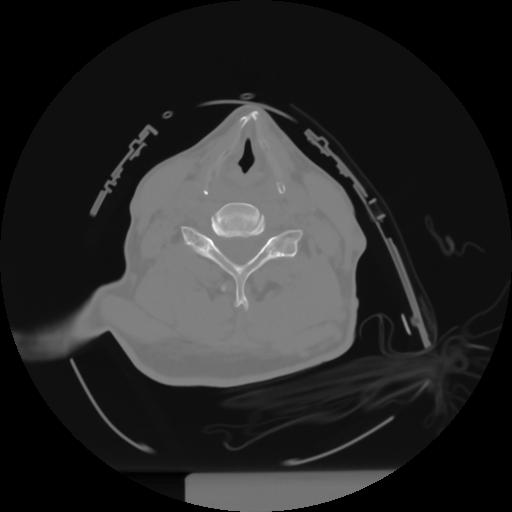

10 P.BLANDAS,,Axial,2.0,P.BLANDAS,,